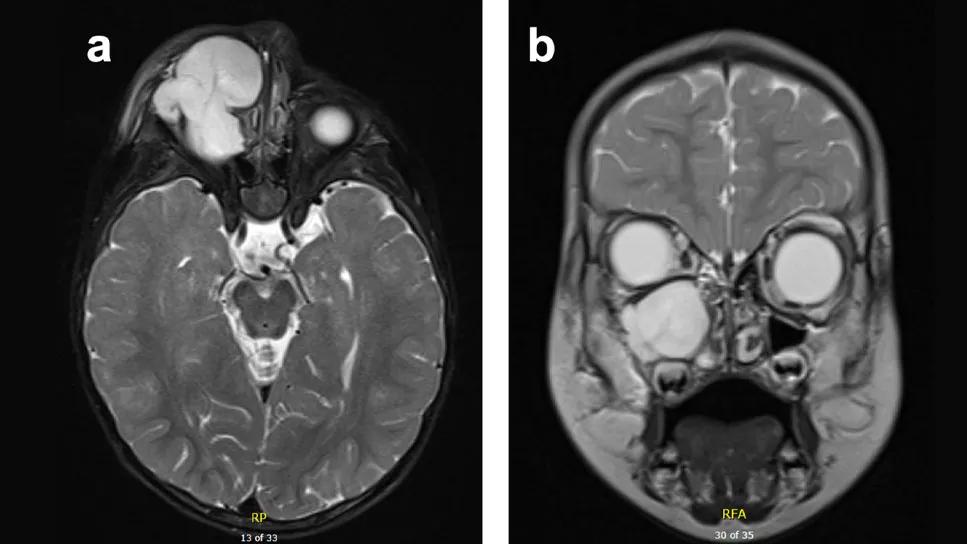

T2 Magnetic Resonance Imaging (MRI) of maxillary sinus mass with extraconal intraorbital extension

During the physical examination, Dr. Georgopoulos observed facial swelling in the right infraorbital region with no overlying erythema or induration. A mass in the maxillary sinus with extraconal intraorbital extension was found via magnetic resonance imaging (MRI). Positron emission tomography (PET) scan showed a non-FGD avid expansile large soft tissue mass in the right maxillary sinus.

Above: Computed Tomography (CT) scan of facial bone demonstrating mass involvement of right orbital rim. At top of page: T2 Magnetic Resonance Imaging (MRI) of maxillary sinus mass with extraconal intraorbital extension